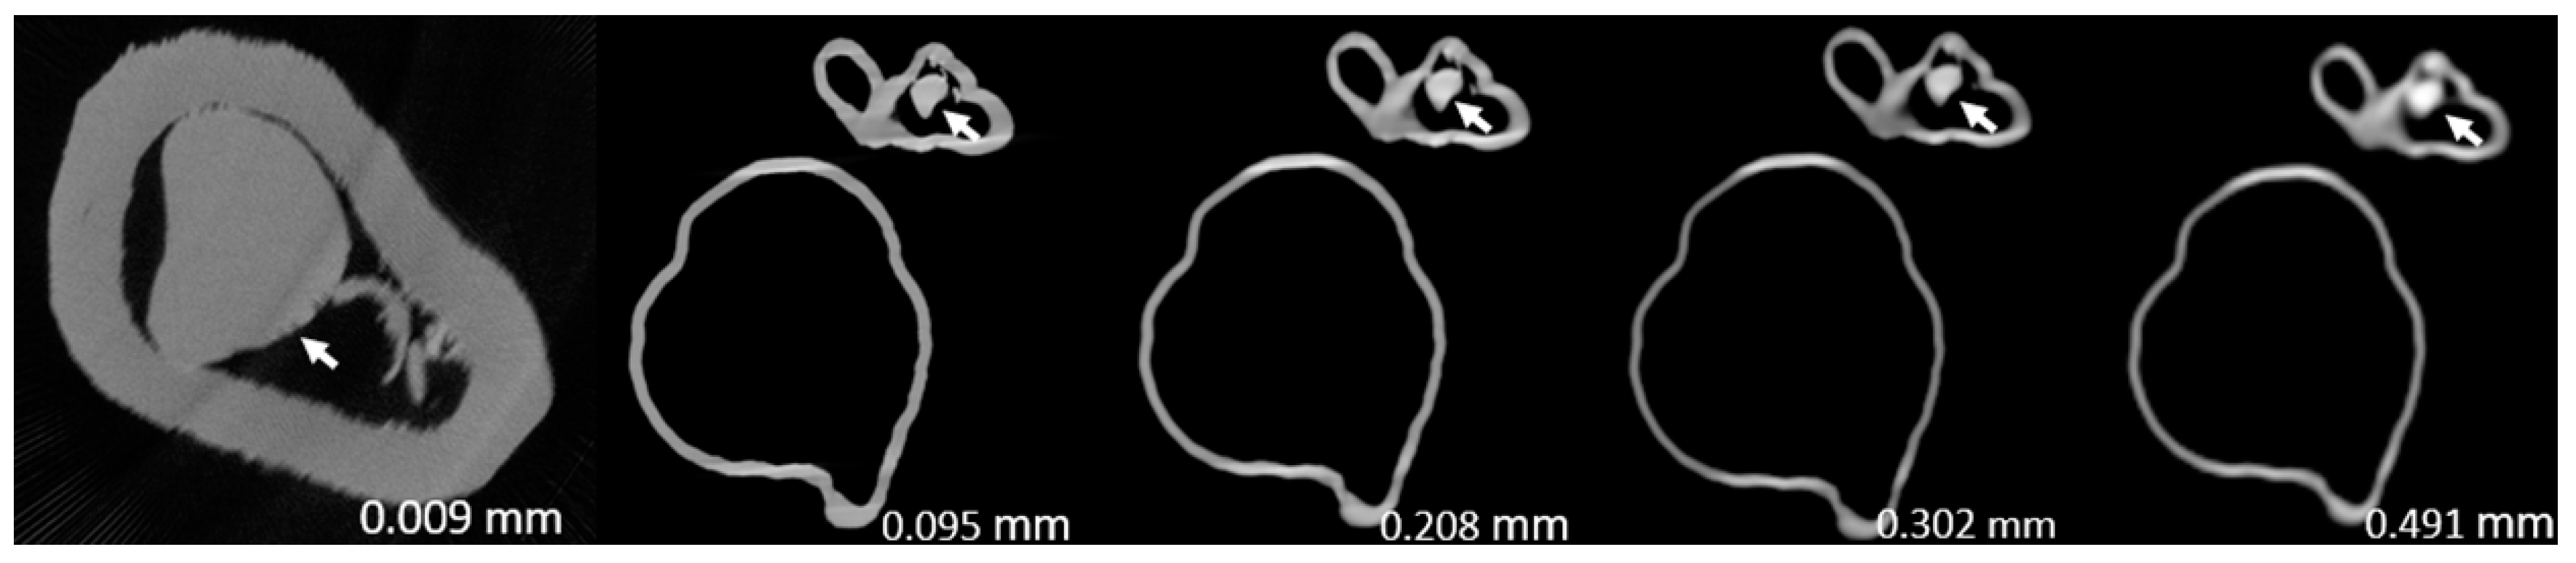

Figure 3, Figure 4, Figure 5, Figure 6, Figure 7 and Figure 8 show the micro-CT and SRCT images of plaques 1 and 2 in models 1-3 that were used for the stenosis assessments. For the micro-CT (0.009 mm slice thickness) images, only the stenotic areas were illustrated due to the processing power limit of the workstation for handling data with a very large matrix (7872×7872). The micro-CT (0.009 mm slice thickness) images were able to clearly demonstrate patent areas between the calcification and the left coronary arterial walls, especially in severe stenosis compared with SRCT (0.095-0.491 mm slice thickness) images (Figure 3, Figure 4 and Figure 5 with >90% stenosis).

Figure 3. Two-dimensional micro-computed tomography (micro-CT) (0.009 mm slice thickness) and synchrotron radiation CT (0.095-0.491 mm slice thickness) images of plaque 1 in model 1 causing >90% stenosis (reprint of synchrotron radiation CT images with permission [15]).